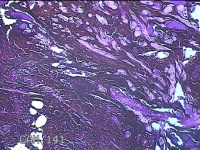

右手臂伸侧肿物

性别

女

年龄

27岁

临床诊断

纤维瘤病

一般病史

下腹部坠胀三天。

标本名称

大体所见

灰褐色肿物0.5x0.3x0.2cm一个,表面糜烂。